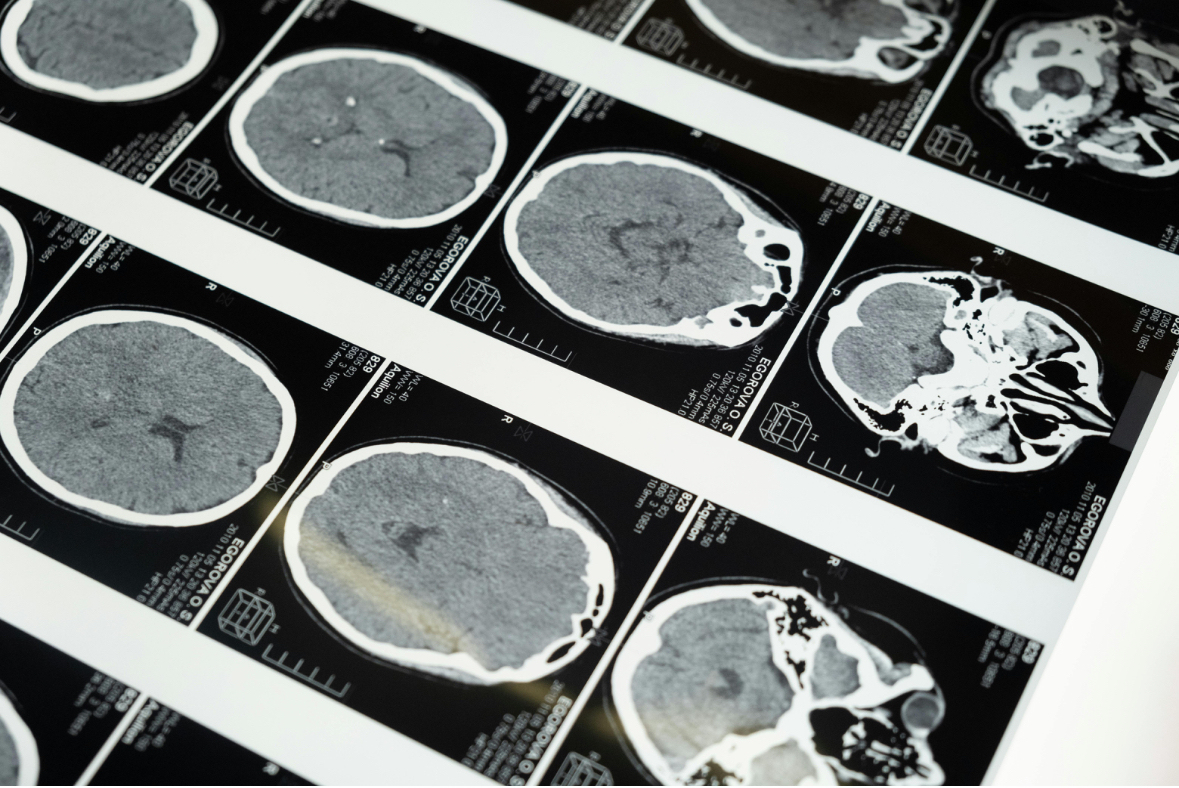

뇌종양의 진단 방법

MRI(자기공명영상)

가장 정확하게 종양 위치와 크기를 확인할 수 있습니다.

CT 검사

응급 상황에서 빠르게 종양 여부를 확인하는 데 유용합니다.